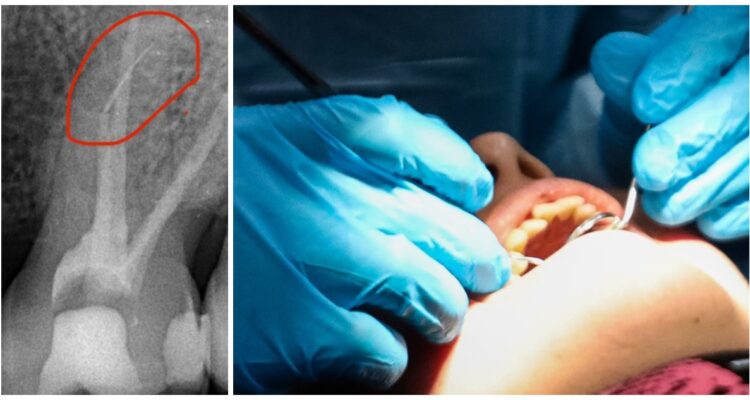

Un paciente denuncia una negligencia médica luego que quedara con un trozo de lima en la mandíbula tras someterse a un tratamiento de conducto en una clínica de Valdivia. El afectado se querelló contra la odontóloga y una demanda civil en control en centro dental.

Hombre terminó con trozo de lima en la mandíbula tras tratamiento de conducto en clínica de Valdivia